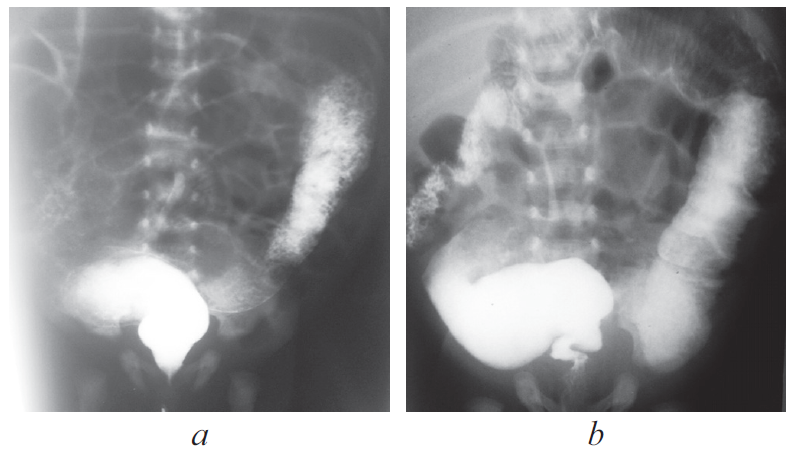

Болезнь Гиршпрунга, как правило, проявляется в первые дни жизни ребенка. Существование различных форм и вариантов ее проявления является основной причиной того, что у части пациентов заболевание не диагностируется в периоде новорожденности. C 2008 по 2019 г. в Детском городском многопрофильном клиническом специализированном центре высоких медицинских технологий г. Санкт-Петербурга находились на лечении 75 детей разного возраста с различными формами болезни Гиршпрунга. В 21 случае диагноз не был установлен сразу после рождения. У 11 новорожденных симптомы заболевания были неяркими и купировались сразу после опорожнения кишечника. У 2 детей с сопутствующей генетической патологией болезнь Гиршпрунга была заподозрена поздно, в связи с имеющимися особенностями опорожнения кишечника у этой группы больных. У части пациентов заболевание проявилось в виде стойкой задержки стула в более старшем возрасте. В статье приведены клинические примеры основных диагностических ошибок у пациентов с болезнью Гиршпрунга или подозрением на нее. Ошибки диагностики у детей раннего возраста связаны как с отсутствием хирургической настороженности у неонатологов родильных домов и отделений новорожденных, так и неправильной трактовкой клинической и рентгенологической картины. Дети в течение многих лет могут наблюдаться и лечиться у различных специалистов, прежде чем попадут в поле зрения детского хирурга.